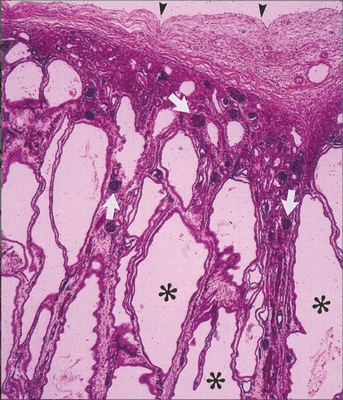

Рисунок 3 | Микропрепарат почки пациента с ПБК-АР. Двадцатикратное увеличение, окраска гематоксилин-эозин.

✱ — радиальные почечные кисты;

▼— почечная капсула.

Стрелками обозначены нормальные клубочки между расширенными собирательными канальцами.